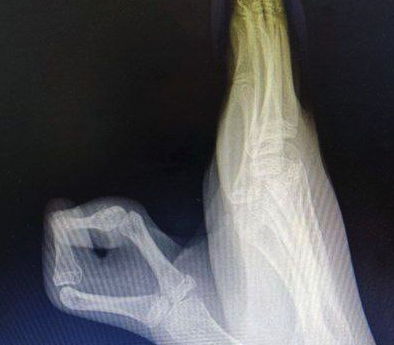

Врачи ОКБ №2 в Тюмени успешно провели операцию по удалению шестого пальца на руке у 12-летней девочки. У пациентки была врожденная аномалия, и родители долгое время откладывали операцию, опасаясь за здоровье ребенка. Хирурги успешно справились с задачей, фаланга срослась. В скором времени девочке извлекут спицы, и она приступит к курсу реабилитации.